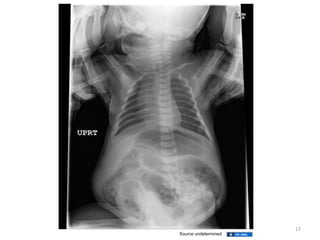

Malrotation with volvulus

Malrotation

• Incidence of malrotation is 1 in 500 live births

• Malrotation with midgut volvulus is the most

• Duodenal intestinal loop comes out but does